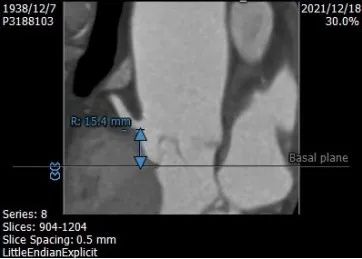

左右冠开口高度:15.4 mm、15.4mm